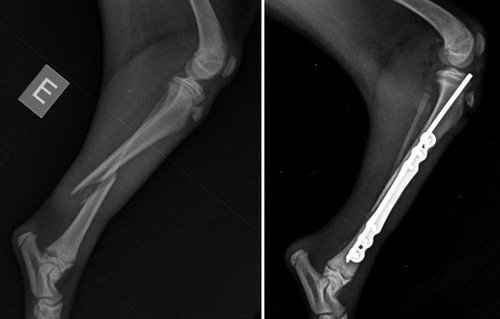

Eu sou a Patricia, e vim fazer essa vaquinha para ajudar a custear a cirurgia da minha cachorrinha Suzi. Ela é uma pinscher de apenas 3 meses que caiu no quintal de casa e acabou fraturando sua perninha, precisando passar por uma cirurgia onde necessitou-se colocar placas e pinos. E no momento estou sem condições de pagar a dívida. Por favor, quem puder ajudar com qualquer valor será bem vindo.